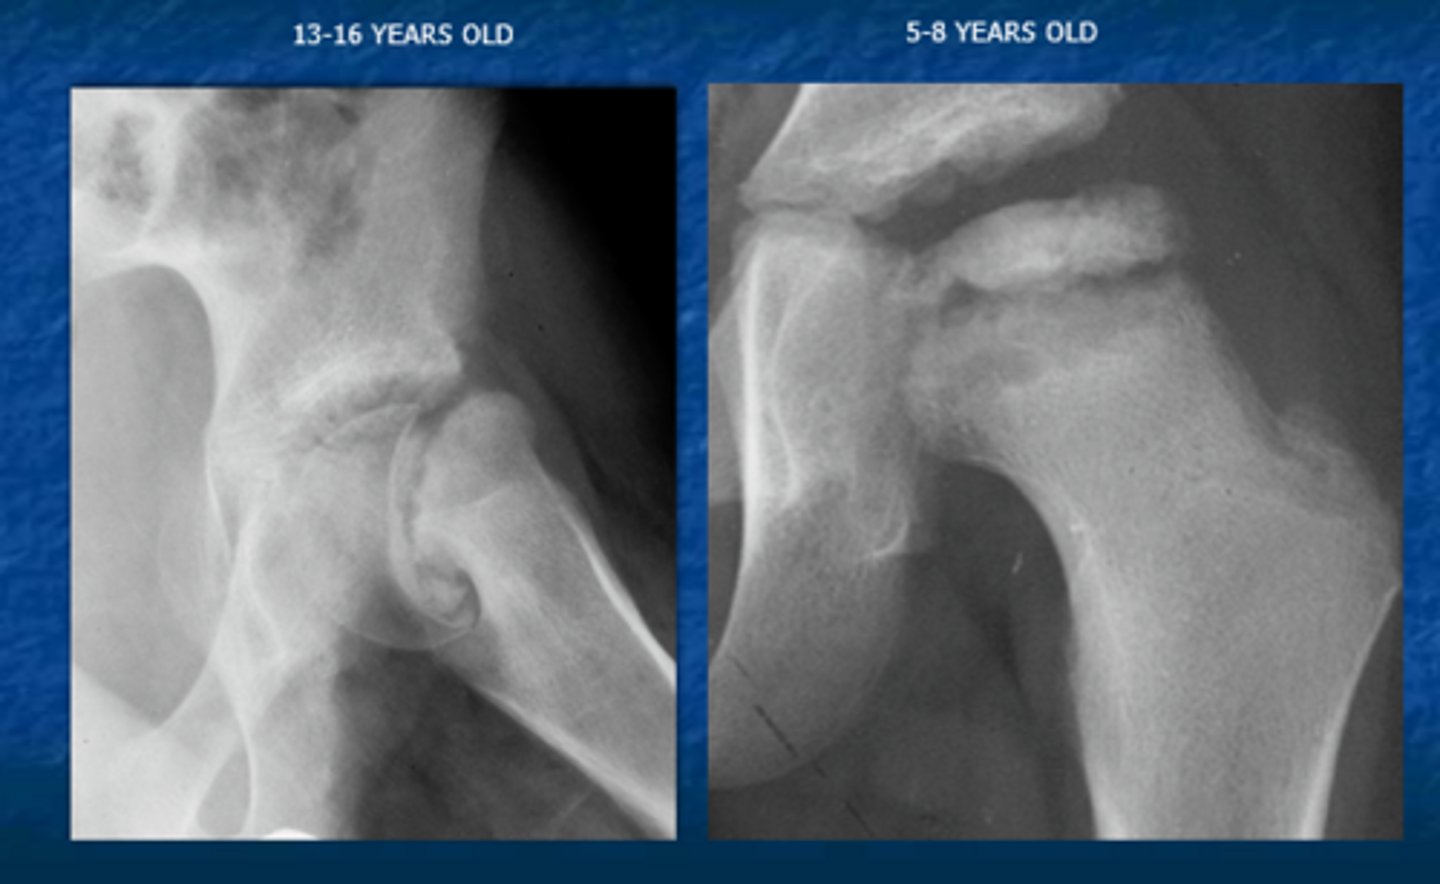

Based on the two age ranges what do each of these individuals have respectively?

Answer

13-16 y/o: SCFE

5-8 y/o: Leggs Cathe Perthes

Leggs Cathe Perthes

Congenital AVN of the hip commonly in children around 4-8 y/o